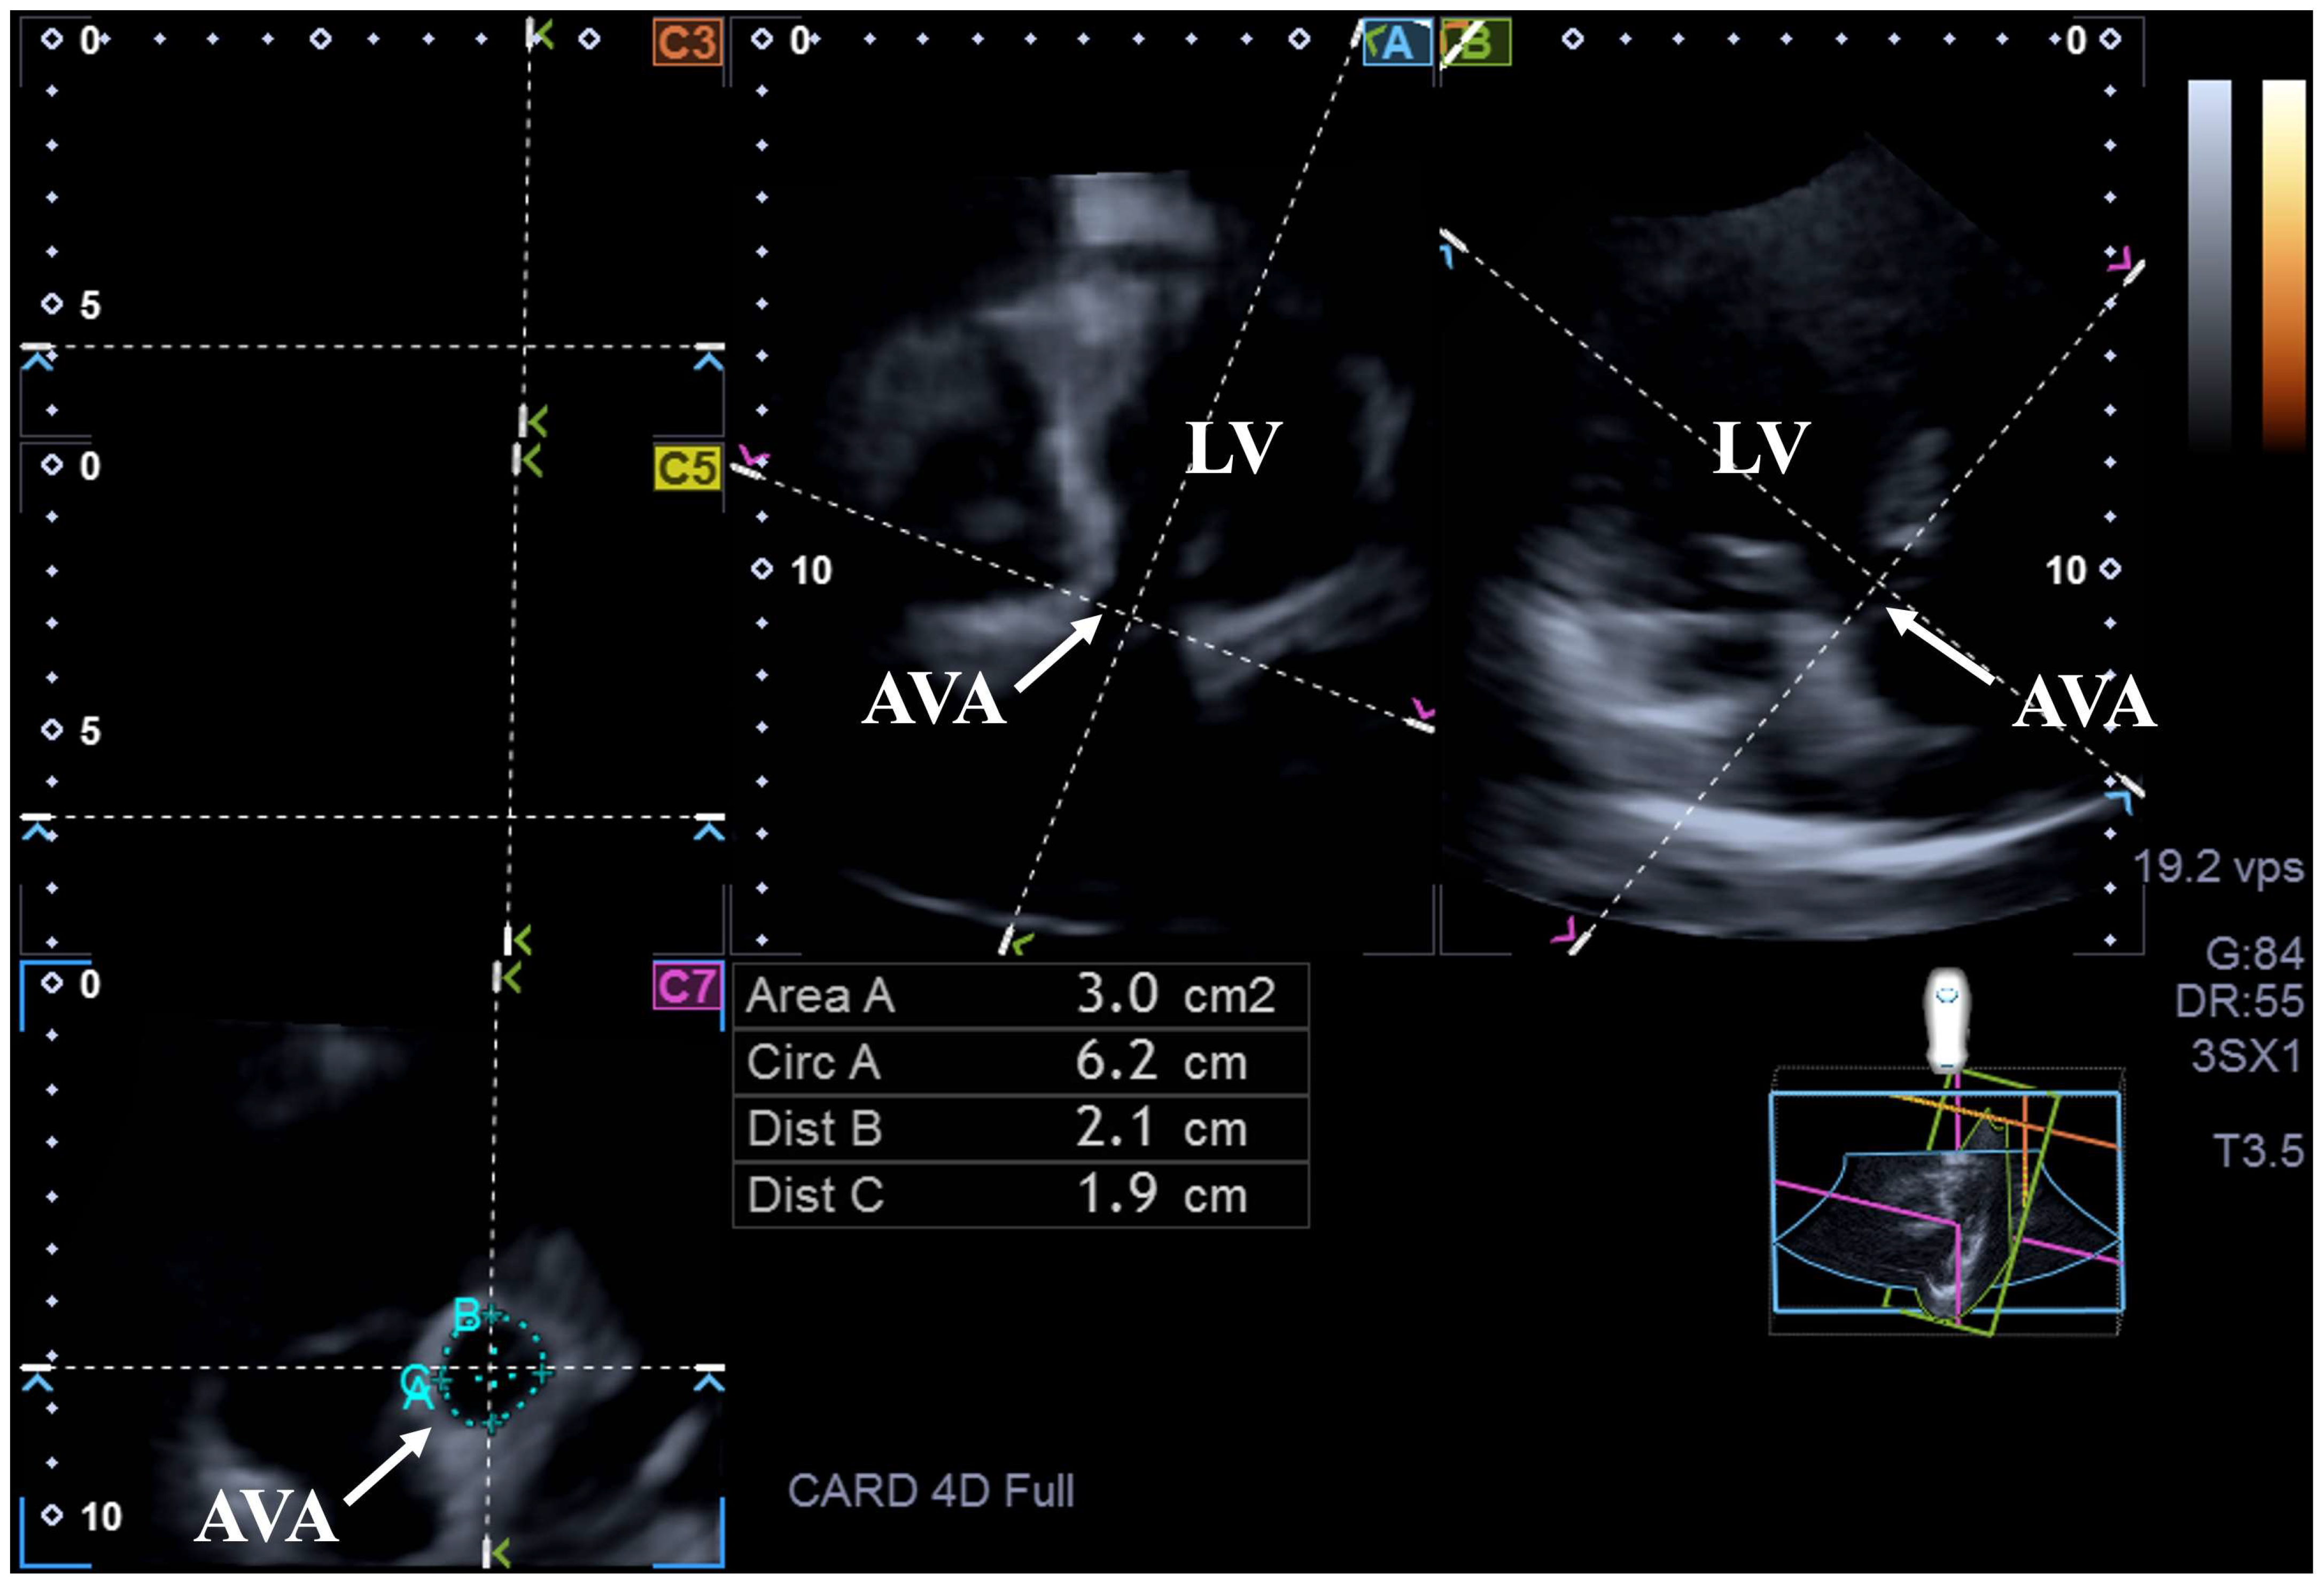

2. Materials and Methods